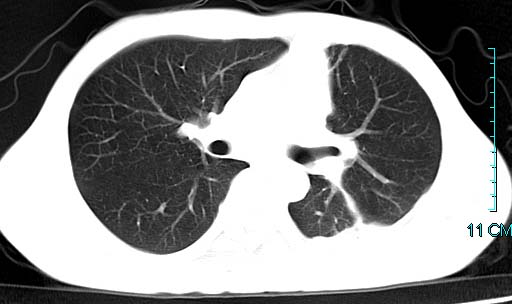

以下是引用qian在2006-3-28 14:32:00的发言:[br]左肺下叶大片状阴影,密度不均,见有条片影和空洞及气液平,少量胸腔积液伴有胸膜增厚,从图像看积液密度比水的密度高,结合病史,考虑左下肺化脓性炎症伴有脓胸。

以下是引用wawaquan在2006-3-28 22:25:00的发言:[br]左上肺舌段多发斑片影。结合“男24y咳嗽咳痰气促伴高热(38.5--39.5)20多天”及穿刺史,[br]考虑1 左下肺化脓性炎症;2脓胸。

以下是引用乡医在2006-3-28 18:37:00的发言:[br]左侧多发液气平面结合患者男24y咳嗽咳痰气促伴高热(38.5--39.5)20多天,查胸水:ldh239.3,总蛋白59.19,tb-ab阴性,利凡它试验+,红c2.7*109,白c1.08*109,分类淋巴92%分叶8%,考虑1脓胸2肺隔离征感染